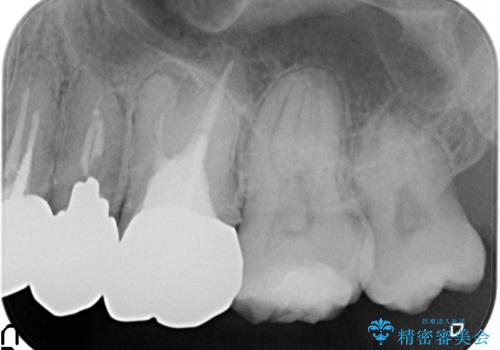

銀歯を除去したところ歯茎よりも深い位置まで虫歯があったため、歯冠長延長術(歯周外科)を行いました。

その後歯茎の回復を待つ間に再根管治療を行い、歯茎の回復後オールセラミッククラウンにて補綴を行いました。

虫歯治療について

虫歯治療は虫歯の進行度によって処置が変わってきます。

虫歯が小さければ、インレー・クラウン等による修復・補綴処置を行うだけで済みます。

しかし虫歯が大きくなると神経処置や抜歯等をしなければならない場合もあります。

虫歯が進み歯茎より深くなってしまうと、虫歯を取り残してしまうリスク、樹脂の硬化の妨げ、補綴物の不適合、歯肉炎・歯周病のリスクの増大等様々な弊害が起こり得ます。

そのため当院では歯周外科手術(歯茎を下げる手術)や歯の挺出による、虫歯が歯茎より深いという問題の解決を推奨しております。